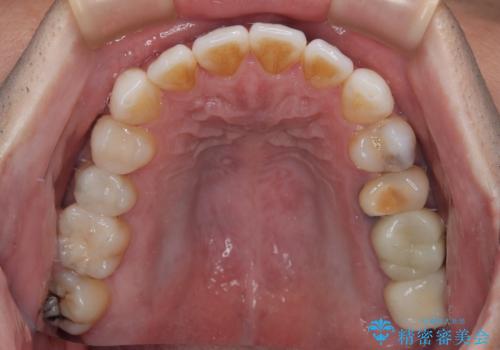

銀歯をなくしたい 全顎的なむし歯治療

その他は銀歯のインレー(部分的な詰め物)が装着されており、それらはむし歯を除去した後にセラミックインレーにて修復治療を行い、左下と根管治療を行う左上の奥歯はオールセラミッククラウンにて補綴治療を行うこととしました。

目立っていた銀歯がなくなり、患者様には大変満足していただけました。